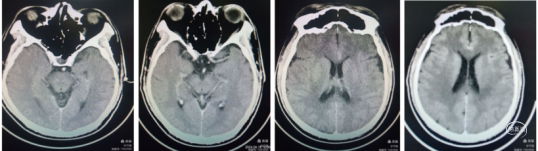

复查CT:左侧大脑中动脉M3、M4段区域浅淡低密度影,脑中线略偏移。无出血,

24小时复查CT内囊梗死部位高密度改变,考虑再通后出血,1周后积血吸收。

术后24小时:复查CT,右侧上干浅淡低密度改变,内囊区域略高密度改变,可能微出血或造影剂未完全排泄。

术后24小时:复查CT术前梗塞区片状浅淡低密度影,脑组织略肿胀。患者意识清,言语清晰正常,左侧下肢肌力3级+,上肢肌力2级。